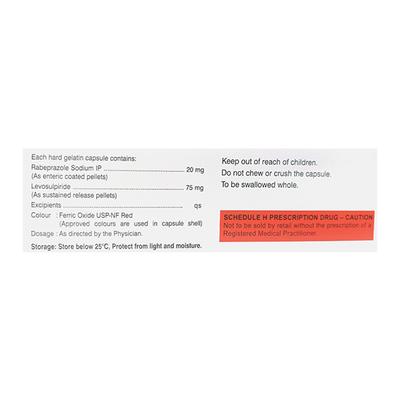

RABETERO L is a combination of Levosulpiride and Rabeprazole which belongs to the group of medicines called Dopamine D2 antagonists and Proton-pump inhibitors respectively. RABETERO L is indicated for the management of Gastro-esophageal reflux disease (GERD). GERD is a chronic digestive disease in which the stomach acid frequently flows into the esophagus leading to irritation and inflammation of lining of food pipe. Symptoms include heartburn, chest pain, nausea, sensation of lump in throat and stomach discomfort.

RABETERO L can also be used to manage peptic ulcer (painful sores in the gut), Zollinger-Ellison syndrome (tumors in pancreas causing the stomach to secrete more acid), functional dyspepsia (recurrent signs and symptoms of indigestion without an obvious cause) and diabetic gastroparesis (delayed gastric emptying caused due to diabetes).

Take RABETERO L preferably on an empty stomach. Avoid consumption of alcohol while taking RABETERO L as it could potentiate the CNS depressive side effects.

Patients receiving long-term management (>1 year) with RABETERO L should be kept on regular surveillance because it can increase the risk of bone fracture (i.e., in the hip, wrist or spine) which is more predominant in the patients having osteoporosis or taking corticosteroids.

Before taking RABETERO L, inform your doctor if you have any heart, kidney or liver disease as a precaution. RABETERO L is not recommended for use in pregnant or breastfeeding women, including children and adolescents (aged below 18 years).

The most common side effects of taking RABETERO L are nausea, vomiting, stomach pain, diarrhea, constipation and headache. Consult your doctor if any of these symptoms worsen.

How to use RABETERO L

Take RABETERO L on an empty stomach or as advised by your physician. Swallow RABETERO L as a whole and do not crush or chew the medicine. Your doctor will decide the correct dose and duration of therapy for you depending upon your age, body weight and disease condition.